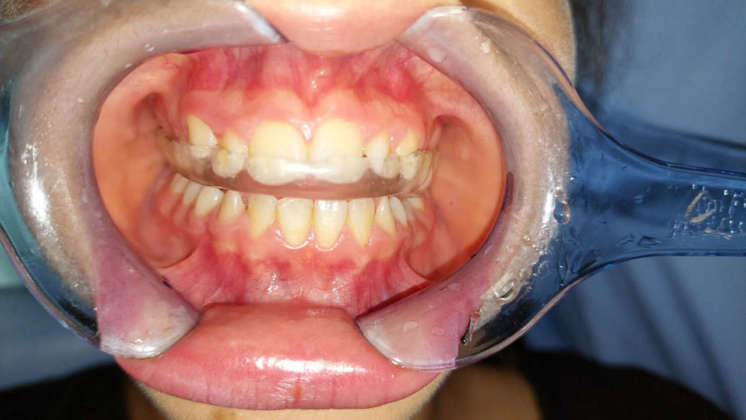

Tecniche di rilassamento psicologico e muscolare sono risultate efficaci nel ridurre i segni di bruxismo nei bambini di età inferiore ai sei anni (31), ma sfortunatamente l’educazione all’autoconsapevolezza e il biofeedback per controllare il bruxismo possono essere una sfida nei bambini. Allo stesso modo, sebbene ampiamente utilizzati per il trattamento del bruxismo negli adulti, i dispositivi orali (OA) non si sono dimostrati parimenti efficaci nei bambini (42) (Figure 1a-d). Probabilmente la causa risiede nelle preoccupazioni relative alla restrizione che si indurrebbe sulla crescita mascellare.

Nonostante ciò, nei bambini con segni e sintomi gravi di TMD, è stato recentemente suggerito l’uso di un OA con una vite di espansione centrale per consentire di seguire il normale sviluppo dei mascellari (43) (Figure 2a-c). Come sottolineato da Castroflorio T et al (19), le abitudini del sonno possono avere un ruolo rilevante nella patogenesi del bruxismo pediatrico, quindi le misure di igiene del sonno non dovrebbero essere a loro volta trascurate. Inoltre, in caso di diagnosi o sospetto di SDB, dovrebbe essere consigliato un trattamento appropriato.